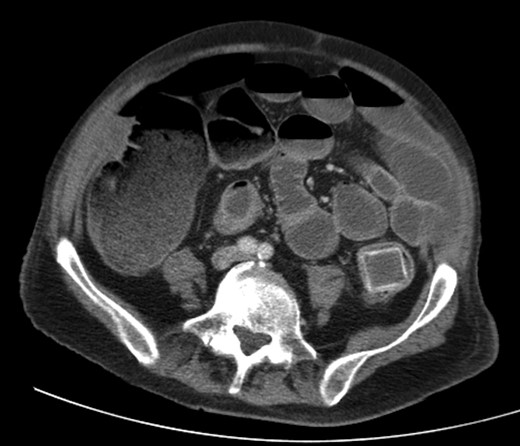

A 92-year male, with no significant co-morbidities apart from peptic ulcers, was admitted with 6 days of obstination. On examination he was dehydrated, with a hugely distended abdomen but no signs of peritonitis. Blood showed features of dehydration and plain abdominal X-ray demonstrated both small and large bowel dilatation, but no obvious causal pathology. A contrast-enhanced computed tomography scan revealed a 2.5-cm partially calcified gallstone impacted at the descending colon-sigmoid junction (Fig. 1). There was no stricture or diverticular disease distal to the stone. A cholecysto-colic fistula could be seen (Fig. 2), with a further smaller gallstone in the caecum (Fig. 3). The offending gallstone could be seen incidentally in the gallbladder on imaging 3 years previously (Fig. 4).

CT reconstruction showing the impacted gallstone and a smaller incidental gallstone in the caecum.